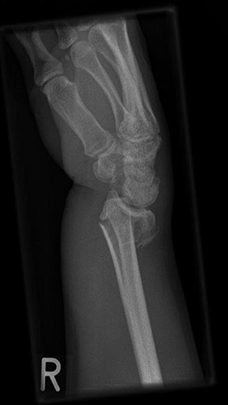

Komplexe rechtsseitige Unterarm-Handgelenksfraktur eines rechtshändigen jungen Mannes. Nach CT-Untersuchung offene Reposition und Rekonstruktion der komplexen Fraktursituation mit angepasster Plattenlänge. Sehr gute Funktion im weiteren Verlauf nach achsengerechter Ausheilung.